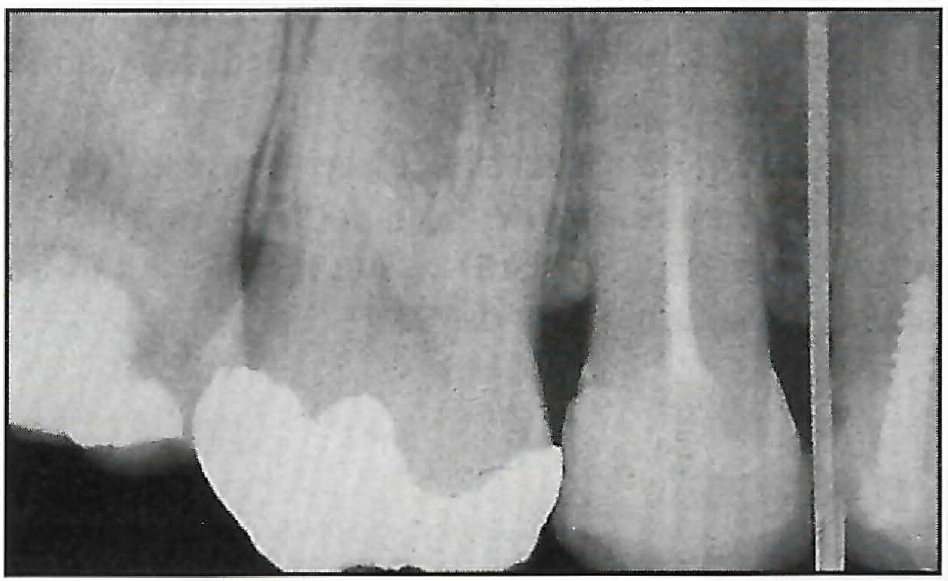

If the screw is to be placed in an area where there is a possibility of damaging adjacent structures, a surgical index should be fabricated from orthodontic wire and thermoplastic or acrylic (Fig. 3). The acrylic fits over the occlusal surfaces of the teeth near the surgical site, and the wire is inserted in the acrylic and bent so that its tip corresponds to the point of screw placement, which is marked with a pressure point or a methylene blue dot on the soft tissue. The distance from the index point to the adjacent anatomic structures can be determined radiographically using the long-cone parallel technique (Fig. 4).

Fig. 3 Acrylic surgical index with orthodontic wire extending to point of screw insertion.

Fig. 4 Radiographic evaluation of screw placement site using surgical index.